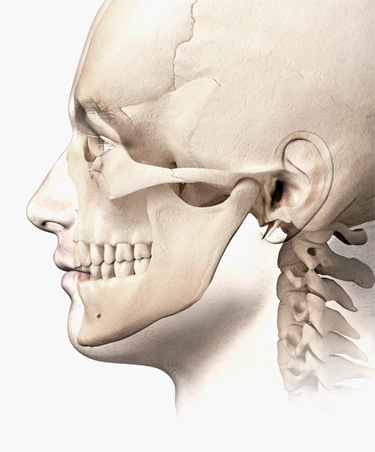

Die Rücklage eines oder beider Kiefer führt immer dazu, dass die oberen Atemwege eingeengt werden.

Bei einer Unterkieferrücklage - ursächlich durch ein unzureichendes Wachstum des Unterkiefers nach vorne - ist meistens der posteroir airway space (PAS), also der hintere Luftbereich im Rachen, reduziert. Oft leiden die Patienten an Übergewicht, was das Schnarchen noch verstärkt. Ein nach hinten fliehendes, kleines Kinn und ein Doppelkinn sind weitere Anzeichen, die in der Profilansicht einfach festgestellt werden können.

Bei einer Oberkieferrücklage liegt meist das Gaumenzäpfchen zu weit im Rachen. Ebenso bildet der Gaumen den Boden der Nase, sodass Fehlstellungen des Oberkiefers deshalb oft mit einer eingeschränkten Nasenatmung verbunden sind. Betroffene atmen vermehrt durch den Mund und schnarchen aus diesem Grund häufig. Weitere häufige Probleme infolge der Mundatmung sind chronische Mandelentzündungen (Tonsillitis) und – weil die Nase als natürlicher Filter der Atemluft ausfällt – Allergien bis hin zu Asthma.